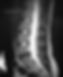

醫生會透過了解病史、檢查肌肉及神經反射狀況來尋找致病原因 ,也會讓病人做些引起疼痛的動作供醫生作判斷,若有需要也會要求患者做磁力共振掃描(MRI),以檢查椎間盤突出有否牽涉周邊脊椎神經線受壓。亦可從磁力共振掃描看見椎間盤失去水分及膠原蛋白而變黑,這就是退化性椎間盤的變化。

從磁力共振掃描看見椎間盤會因為失去水分及膠原蛋白而變黑,這就是退化性椎間盤的變化